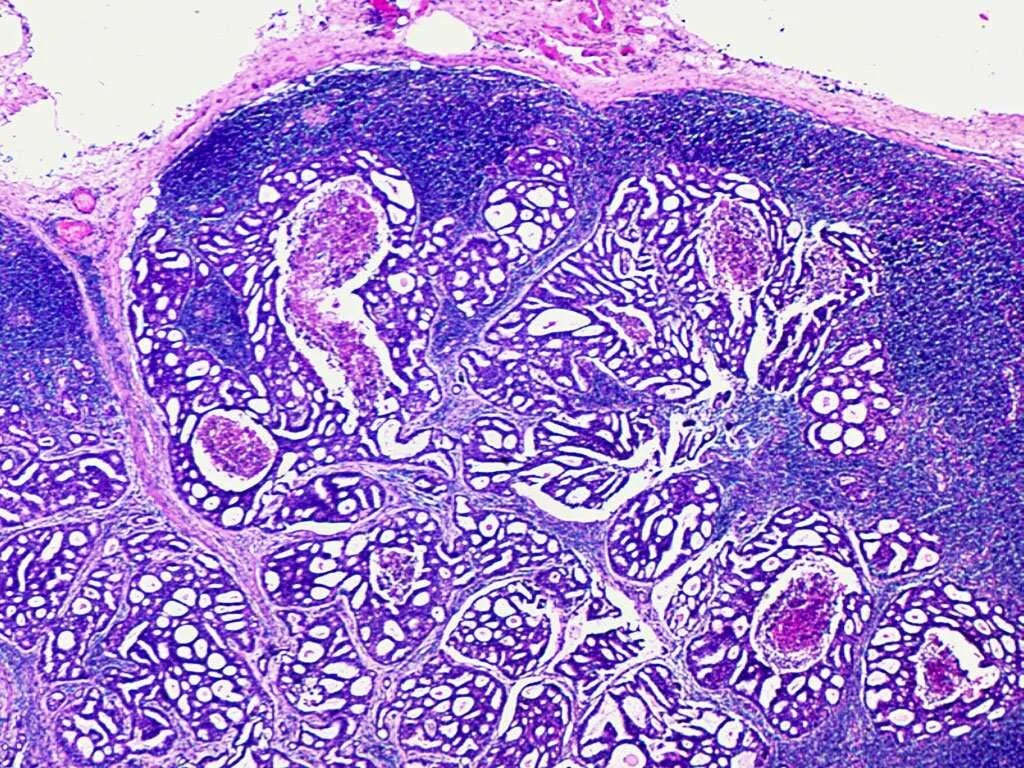

Гистологические варианты